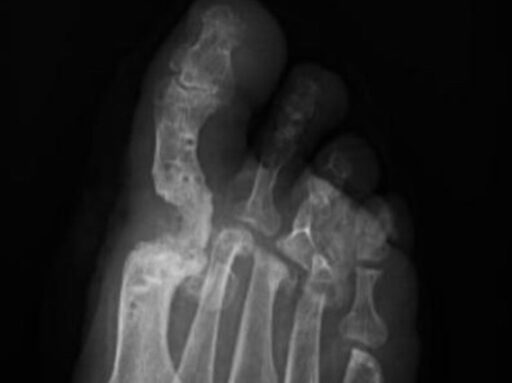

Rescate de pseudartrosis artrodesis de hallux

¿Has escuchado hablar de pseudartrosis y artrodesis de hallux? Estos términos médicos pueden sonar complicados, pero te explicaremos de forma sencilla qué significan y por qué a veces es necesario